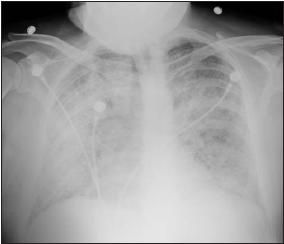

Later that day, the patient became more dyspneic with a concurrent drop in oxygen saturation, requiring an increase in oxygen supplementation. A chest radiograph revealed diffuse alveolar infiltrates (Figure 2).

Figure 2 – Bilateral diffuse alveolar airspace infiltrates are revealed on this portable chest radiograph.